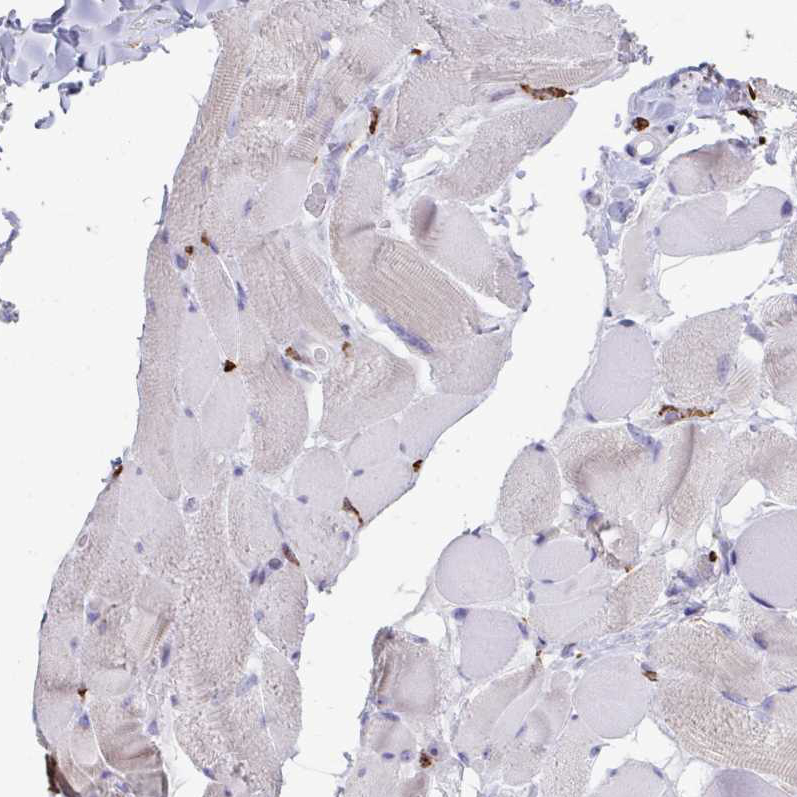

Immunohistochemistry analysis in human spleen and skeletal muscle tissues using HPA051974 antibody. Corresponding CD163 RNA-seq data are presented for the same tissues.